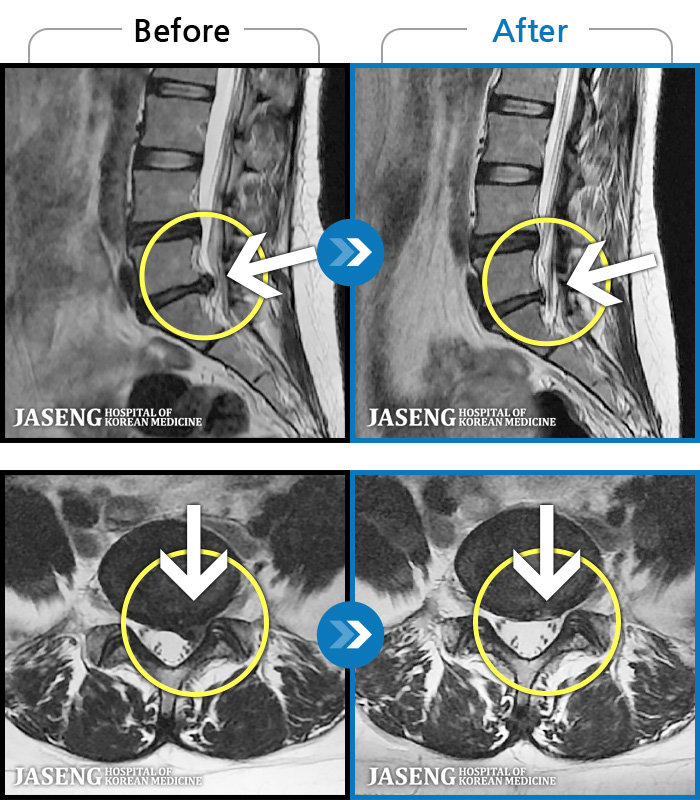

[뱸] 19.11.28~25.05.06

ȯںп Ǹ ǿ ԿǾ, ο ġ ۿ Ƿ ġḦ Ͻñ ٶϴ.